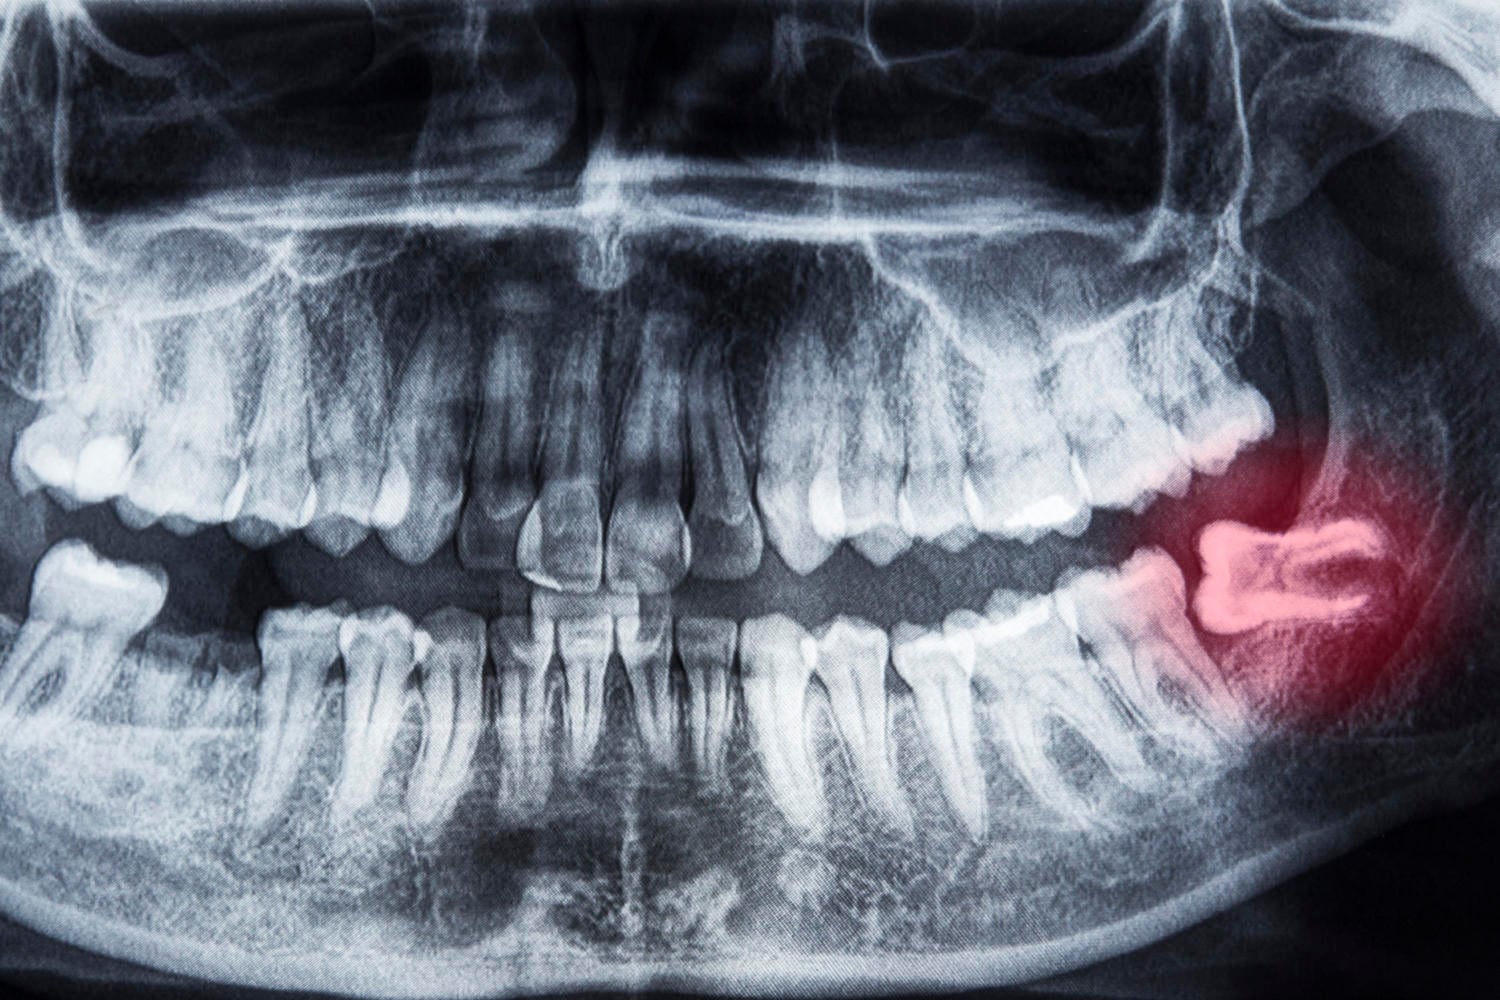

Crescita obliqua del dente del giudizio inferiore (iStock.com/blueshot)

Succede non di rado che un dente del giudizio non riesca a spuntare correttamente e, quando si verifica questa situazione, si parla di “dente incluso”.

- asse di crescita del dente orientato in modo non corretto (in certi casi addirittura in direzione orizzontale, verso il molare già presente).